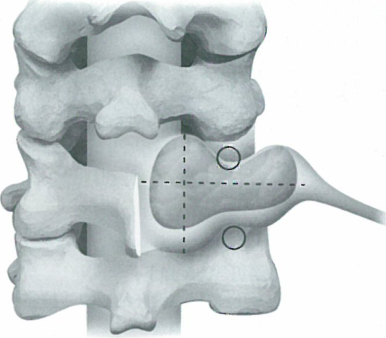

图2 切开横突孔前方并减压

出国看病机构爱诺美康介绍,将腱膜和交感神经链拉向外侧。沿椎体横突和椎体分离颈长肌和头长肌,并将受累节段的该肌肉切除(图2)。将椎体前方肌肉切除后,椎体横突前方便被暴露清除(图2)。切断肿瘤上下邻近椎体的横突前支,操作时要十分小心保护椎动脉周围的骨膜鞘和静脉丛。并非所有的肿瘤包膜都明显,有时可能与骨膜鞘难以区分。将椎动脉拉向前方或侧方,在横突更外缘暴露椎动脉下方的肿瘤。如果电刺激后没有反应可以将该神经根切断。之后从外侧向头端分块切除肿瘤。椎动脉可能向内侧或外侧移位,需要在椎动脉的一侧分块切除肿瘤。如果对电刺激有反应,保留有功能的神经根,或者必须在神经根表面保留部分肿瘤组织。切除硬膜内肿块需要将椎间孔钻大。用限深钻将上一椎体的侧方钻开,这样可以暴露硬膜的前外侧。暴露好硬膜后,纵行切开硬膜。将神经根近端分离后,位于硬膜内的肿瘤便可以被牵拉出并且被切除。